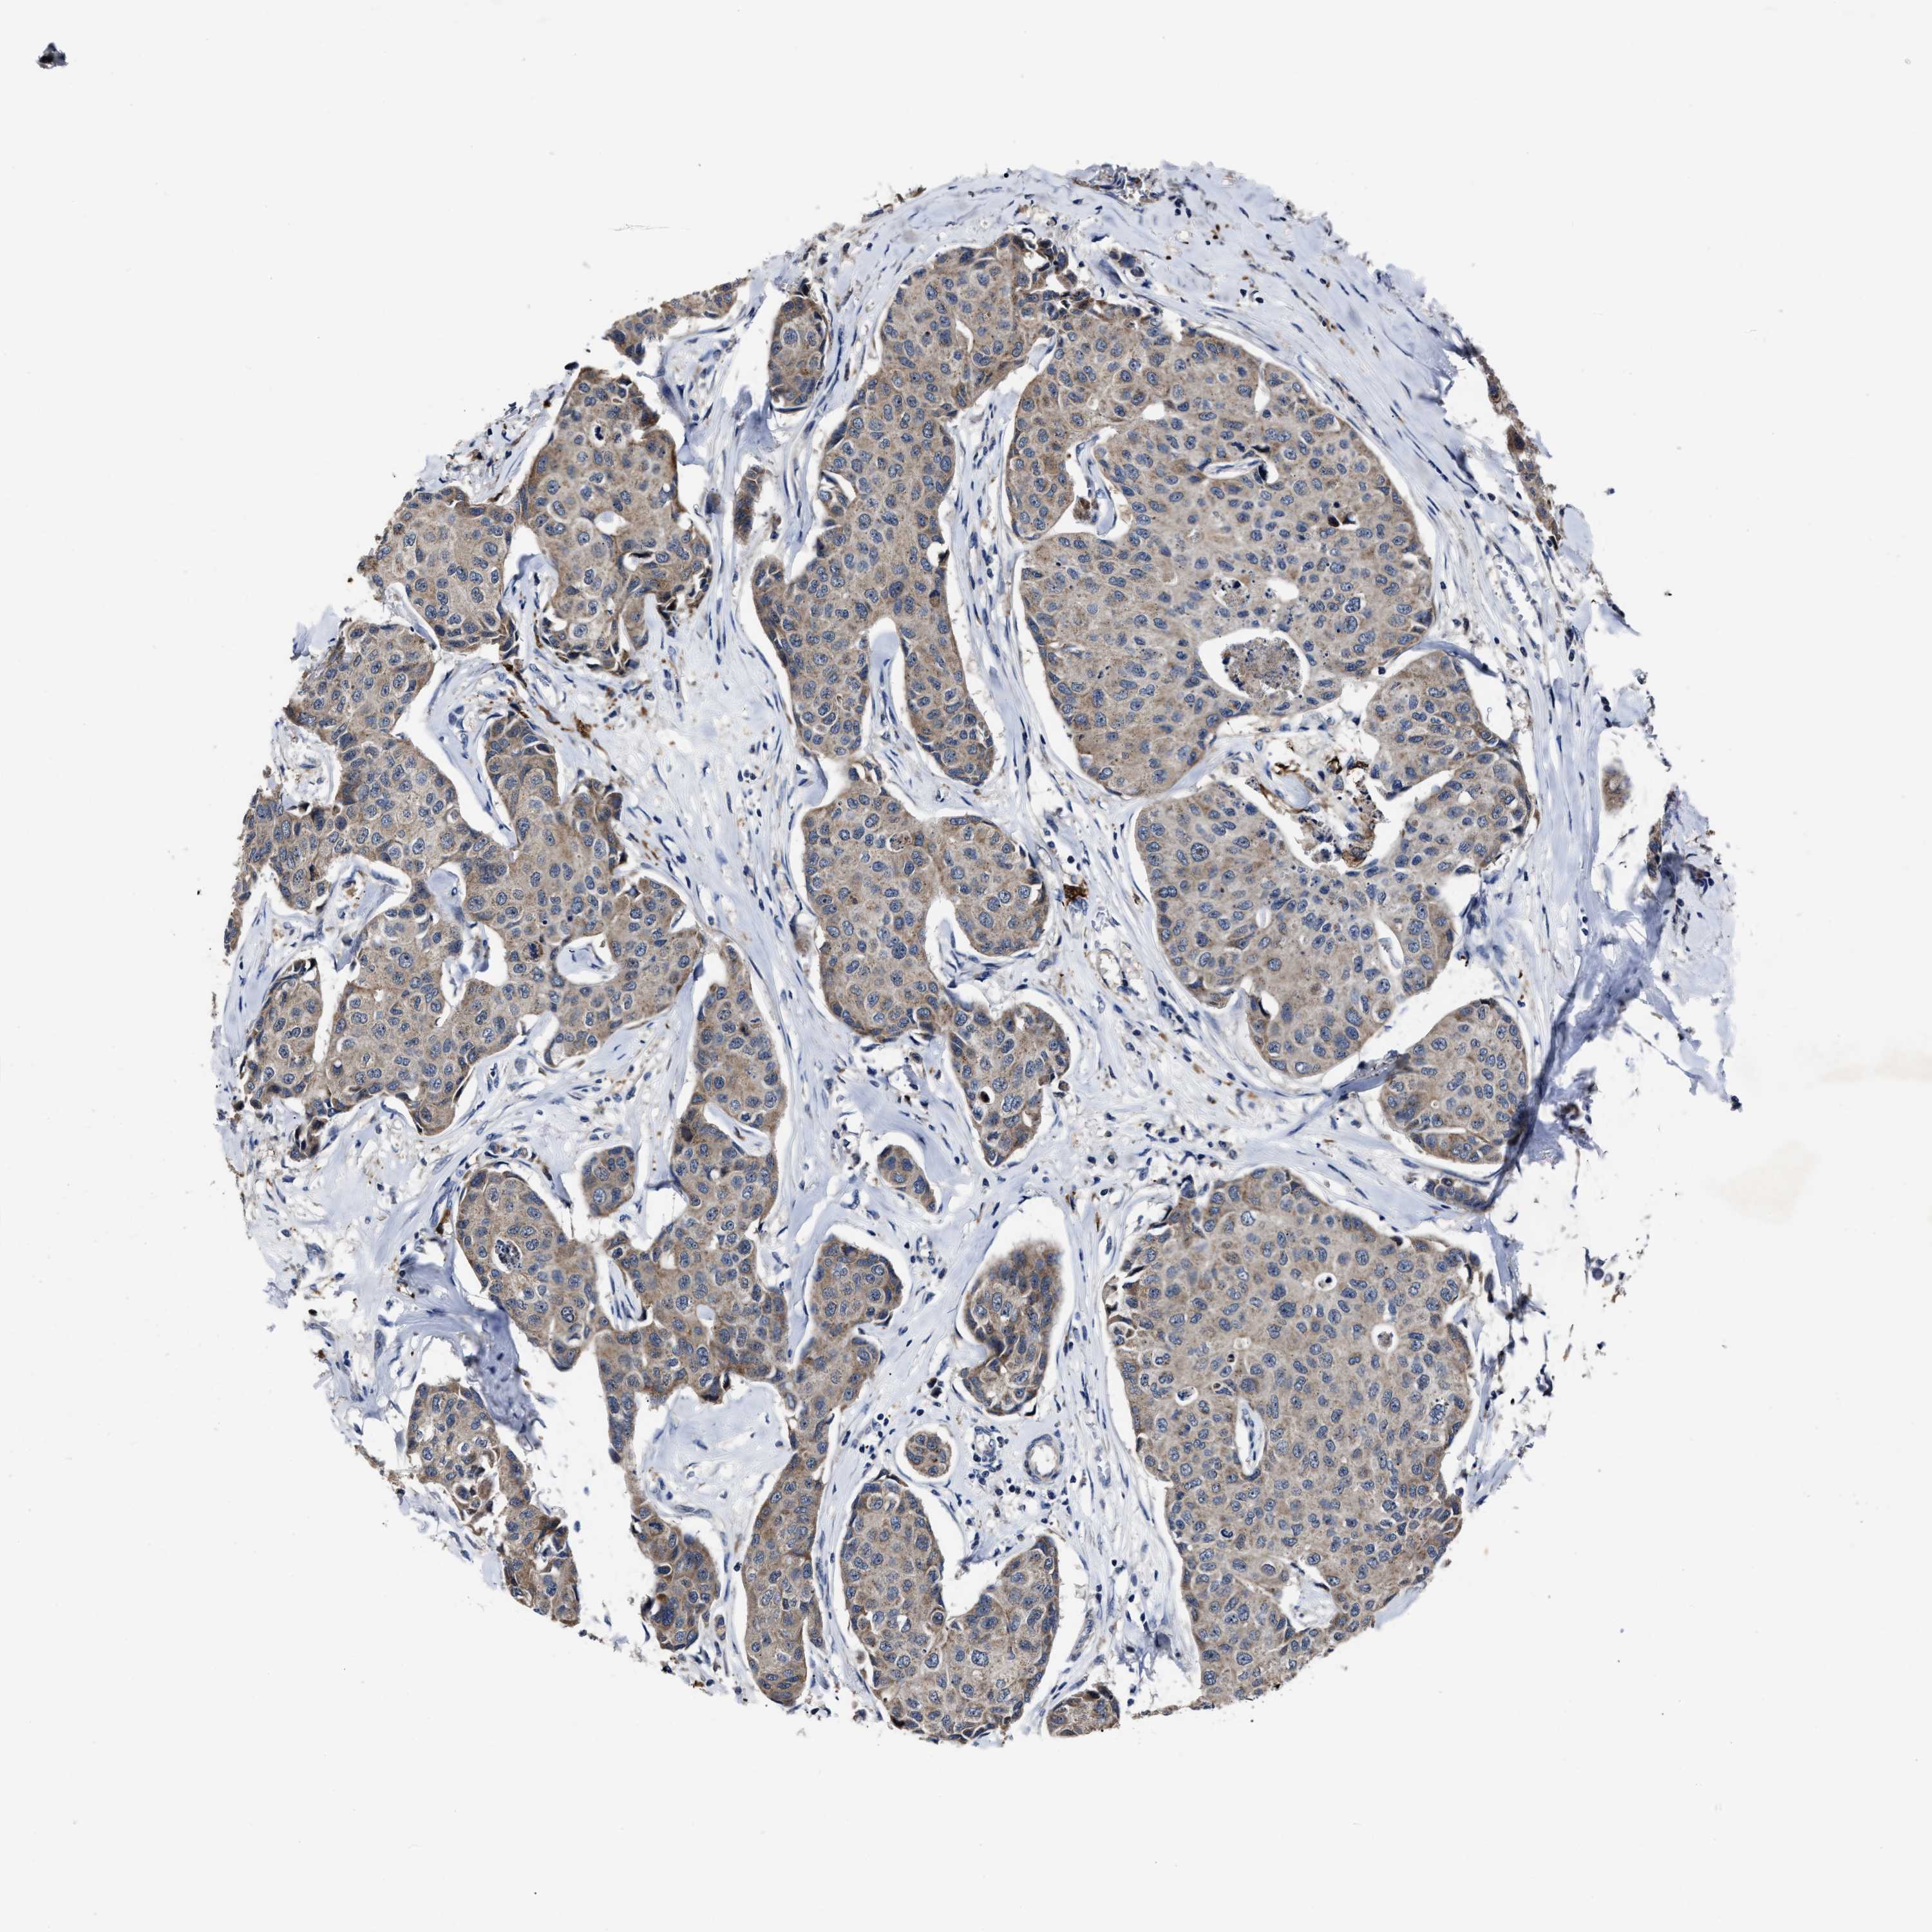

CANCER BREAST CANCER Show tissue menu

BRCA TCGA BRCA VALIDATION PROTEIN EXPRESSION